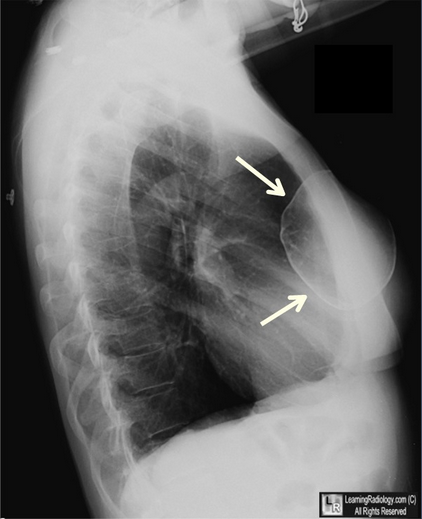

胸部X光片(侧位)

乳腺假体钙化。很薄的钙化曲线围绕在该患者12年前植入的右侧乳腺盐水假体囊周围(白色箭头)。左侧假体比正常乳腺组织密度较高(黄色箭头),但是在该胸片上未见到它的钙化。